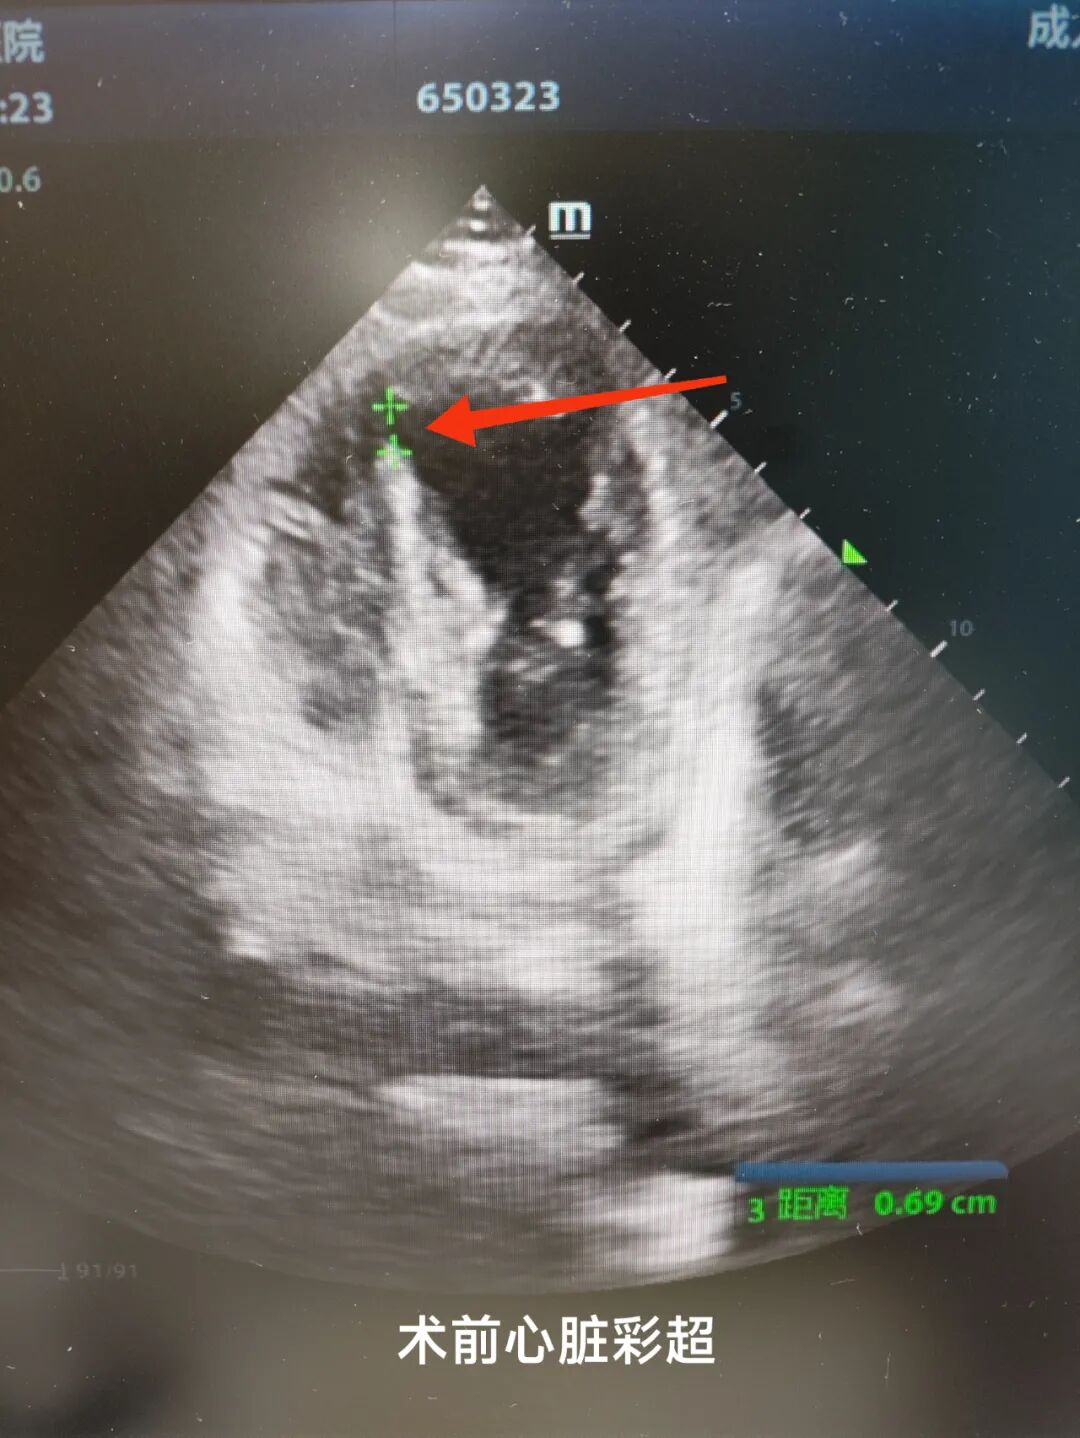

2025年1月,72歲的賴女士突發(fā)持續(xù)性胸痛伴大汗淋漓,當(dāng)?shù)蒯t(yī)院確診為急性廣泛前壁心肌梗死。急診PCI術(shù)中雖開通了堵塞的前降支,但術(shù)后第3天心臟超聲顯示致命性室間隔穿孔(直徑10mm),左向右分流量達(dá)3:1,患者迅速出現(xiàn)急性左心衰、肺水腫,生命體征如同"過山車"般劇烈波動。

轉(zhuǎn)入心外科后完善術(shù)前準(zhǔn)備,在心血管醫(yī)學(xué)中心心臟大血管外科胡名松主任的主持下,經(jīng)心內(nèi)科、內(nèi)分泌科、麻醉科、CCU、手術(shù)室、心臟彩超室多學(xué)科會診全面評估后,心外科團(tuán)隊為患者實施高難度“冠狀動脈旁路移植+室間隔缺損修補(bǔ)術(shù)+室壁瘤切除術(shù)”。術(shù)中成功修補(bǔ)12mm室間隔穿孔,切除異常室壁組織,并完成冠脈血管重建,手術(shù)過程順利,術(shù)中食道超聲實時驗證分流消失。